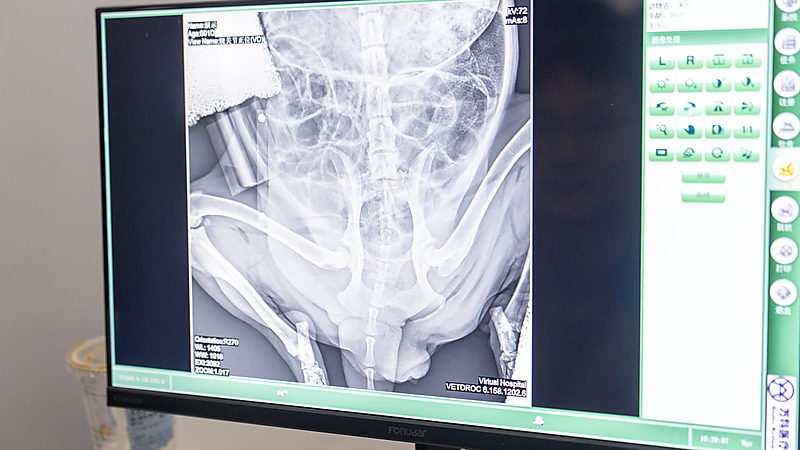

今日第二堂课,由陈炜力老师带来全髋关节置换术(THR)影像学检查专项教学。陈老师重点强调:规范的影像学拍片操作+标准患宠摆位,是 THR 术前精准评估、术中顺利实施与术后效果保障的核心基础。课堂上,他结合多例临床典型病例,围绕拍片完整流程、精准摆位要点、影像判读关键指标展开细致拆解与讲解,帮助在场兽医师系统掌握术前影像学检查规范,为临床安全开展全髋置换手术夯实技术根基。

全髋置换手术能否成功,术前影像学评估是关键基础,也是我们每期课程反复强调的核心要点。标准的术前影像,是手术规划的精准指引,能清晰判断病情、精确测量参数,为患宠选择最合适的植入物,从源头保障手术效果。

随后,陈炜力老师针对学员们实操所拍摄的术后X光片,逐一进行细致分析与专业讲解,耐心点拨片中存在的问题、拆解应对思路,帮助大家规避误区,确保在后续实操中少走弯路、精准规避同类问题,切实提升实操水平。